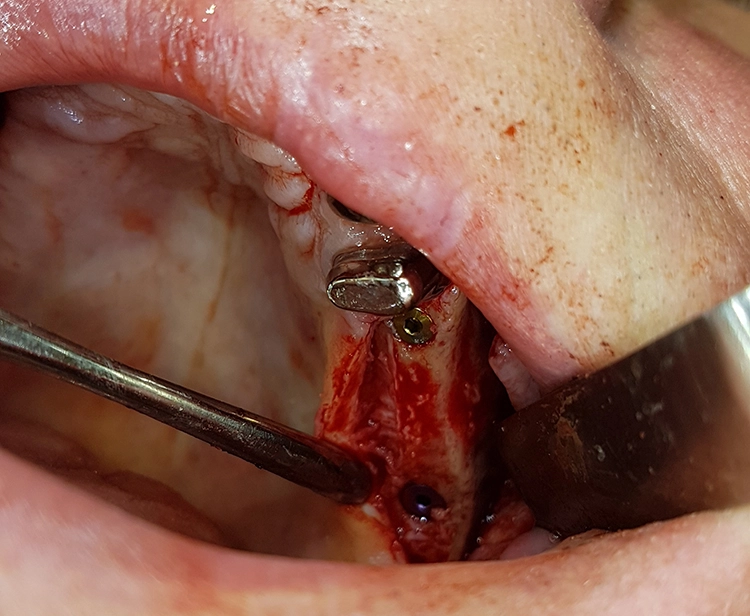

Zeitgleich mit der Freilegung wurde Zahn 13 extrahiert. Nach sorgfältiger Exkochleation wurde die unversehrte Alveole im Sinne einer Socket Preservation mit bovinem Knochenersatzmaterial (MinerOss X) verfüllt und mit einer porcinen Kollagenmembran (MemLok Pliable) abgedeckt. Damit lässt sich ein postoperativer Gewebeabbau und eine Einschränkung der Weichgewebeästhetik unter einem Brückenglied weitgehend vermeiden: Die Socket Preservation mit bovinem Knochenmineral und porciner Kollagenmembran schränkt die horizontale und vertikale Knochenresorption im Vergleich zur alleinigen Extraktion erheblich ein (Abb. 19 und 20) [1,6,9].